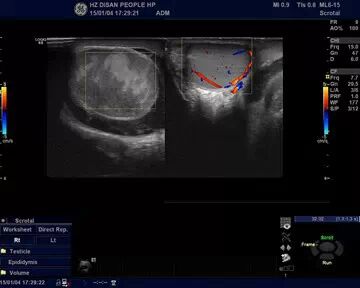

“彩超提示:右側(cè)睪丸未見血流。與首診判斷吻合:睪丸扭轉(zhuǎn)已經(jīng)壞死,需要,急診手術(shù)切除,保護對側(cè)睪丸。”

睪丸扭轉(zhuǎn)B超圖示